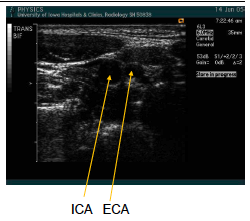

this image is showing…

trans bifurcation (continue to image sup as far as possible) lateral approach

general rules for finding the ICA and ECA

_____ approach, ICA is more often lateral or posterior.

You can tell from the _____ of bifurcation, it will be difficult to get the “Y” view of ICA and ECA together.

If you can not get the “Y” view, you must image each vessel _______.

_____the transducer over the bulb to find the ECA and ICA – see video clip

Lateral

transverse

separately

“Pivot”